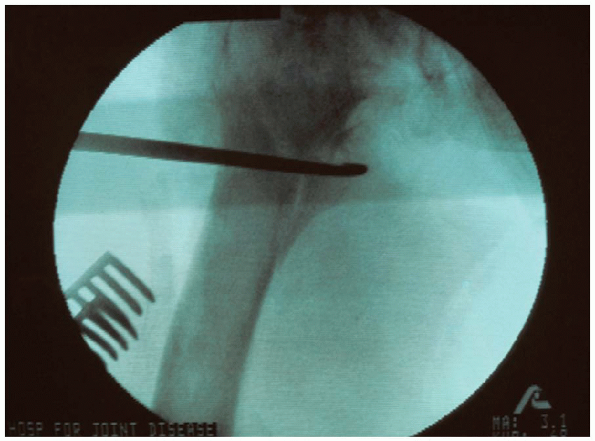

image intensification, a starting point is identified on the lateral

neck and head under image intensification using the 135-degree guide (Fig. 23-12).

position of the guide pin is adjusted until it lies in the center of

the femoral head and neck on the anteroposterior and lateral planes.

FIGURE 23-12.

A starting point is identified on the lateral cortex of the proximal femur, usually at the level of the lesser trochanter, centered between the anterior and posterior cortical margins. A drill hole is made and a guide pin inserted into the femoral neck and head under image intensification using the 135-degree guide. |